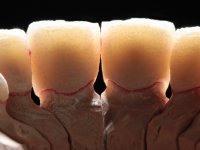

Avaliada a situação inicial em conjunto com o médico dentista, foi considerado prioritário alterar a forma dos dentes, subir 1.5mm a D.V.O. e descruzar a mordida do 1º Quadrante. Na confeção da ponte provisória superior de acrílico com reforço metálico foram já ensaiadas essas alterações. Optamos por um monobloco de 13 dentes com o intuito de manter a estabilidade posicional dos dentes re- preparados. Após remoção das coroas e pontes antigas foi feita a re-preparação dentária. A ponte provisória foi rebasada em boca, primeiro com acrílico auto-polimerizável e depois com resina composta. Após 4 semanas de integração da ponte provisória superior foi confecionada a ponte provisória inferior, corrigindo-se finalmente as discrepâncias existentes no plano oclusal. As impressões foram realizadas com a técnica de dupla mistura, com dupla mistura. Simultaneamente foram feitos os registos da relação inter-maxilar e da relação do maxilar superior com a base do crânio, utilizando o arco facial. Montados os modelos de trabalho em articulador semi-ajustável, foram confecionadas as peças próteticas, utilizando tecnologia CAD-CAM para a realização das infra-estruturas em zircónia. A colocação da cerâmica foi feita procurando que a forma dos dentes reproduzisse uma forma anatómica natural. A tonalidade foi condicionada pela vontade do paciente. Foi feita uma prova com a cerâmica em “biscuit” para verificação técnica e validação estética. Após aprovação pelo paciente o trabalho foi finalizado e colocado em boca.